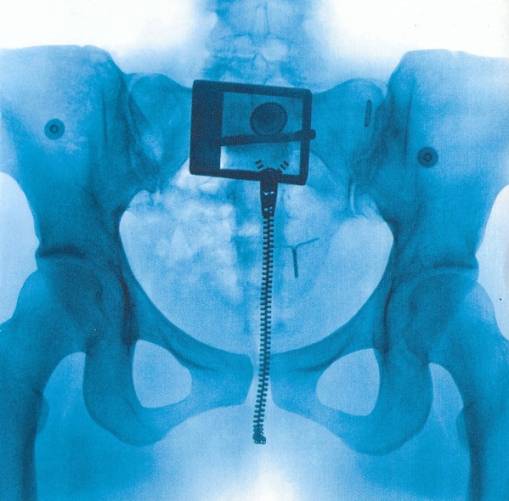

VIRGIN

Wykonawca: LORDE